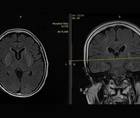

Case Report: Noninvasive Intracranial Pressure Monitoring

Ankit Bansal, MD; Neetika RastogiAnkit Bansal, MD; Neetika Rastogi